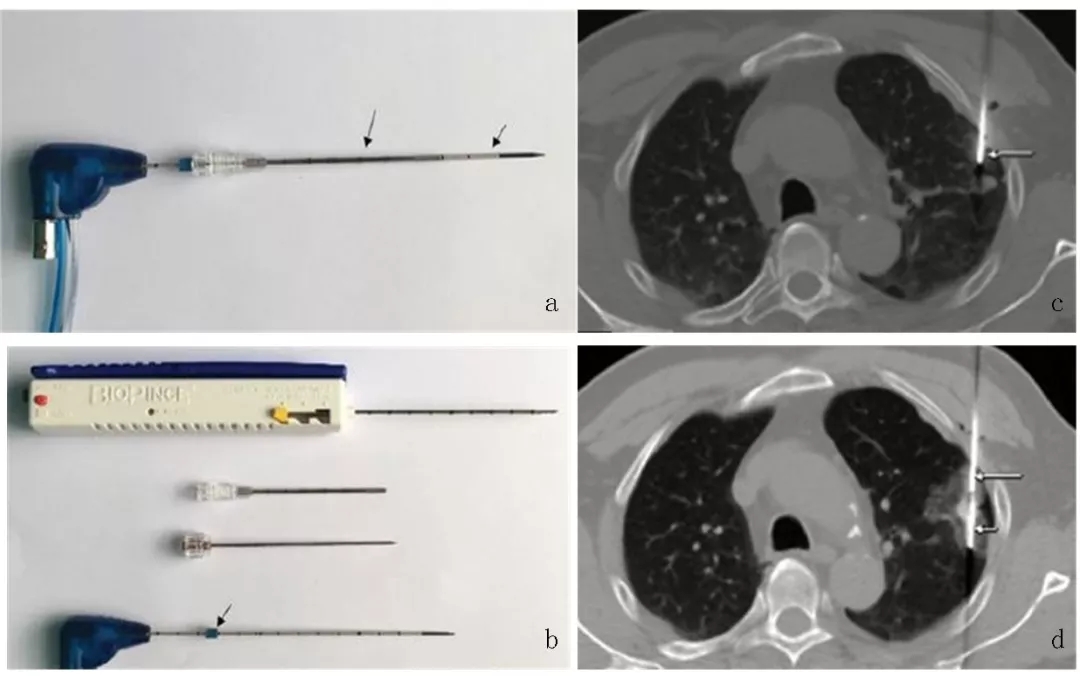

因此,北京医院肿瘤微创治疗中心创新性地使用同轴套管技术同步实施经皮肺穿刺活检及热消融治疗,应用于NSCLC患者的诊疗(图1)。该中心的研究显示,对比序贯活检及消融治疗高度可疑恶性肺结节,同轴套管活检同步消融术可出现更少的并发症并有类似的治疗效果。

图1. 经皮肺穿刺活检同轴套管微波消融术示例。a.MWA针与同轴套管组合(短箭头为消融针,长箭头为同轴套管);b.同轴套管组合原件包括:全自动活检枪、套管针、套管针芯及MWA针;c. CT引导下同轴套管穿刺入病灶内;d.活检后MWA针经同轴套管穿入病灶内实施消融治疗。